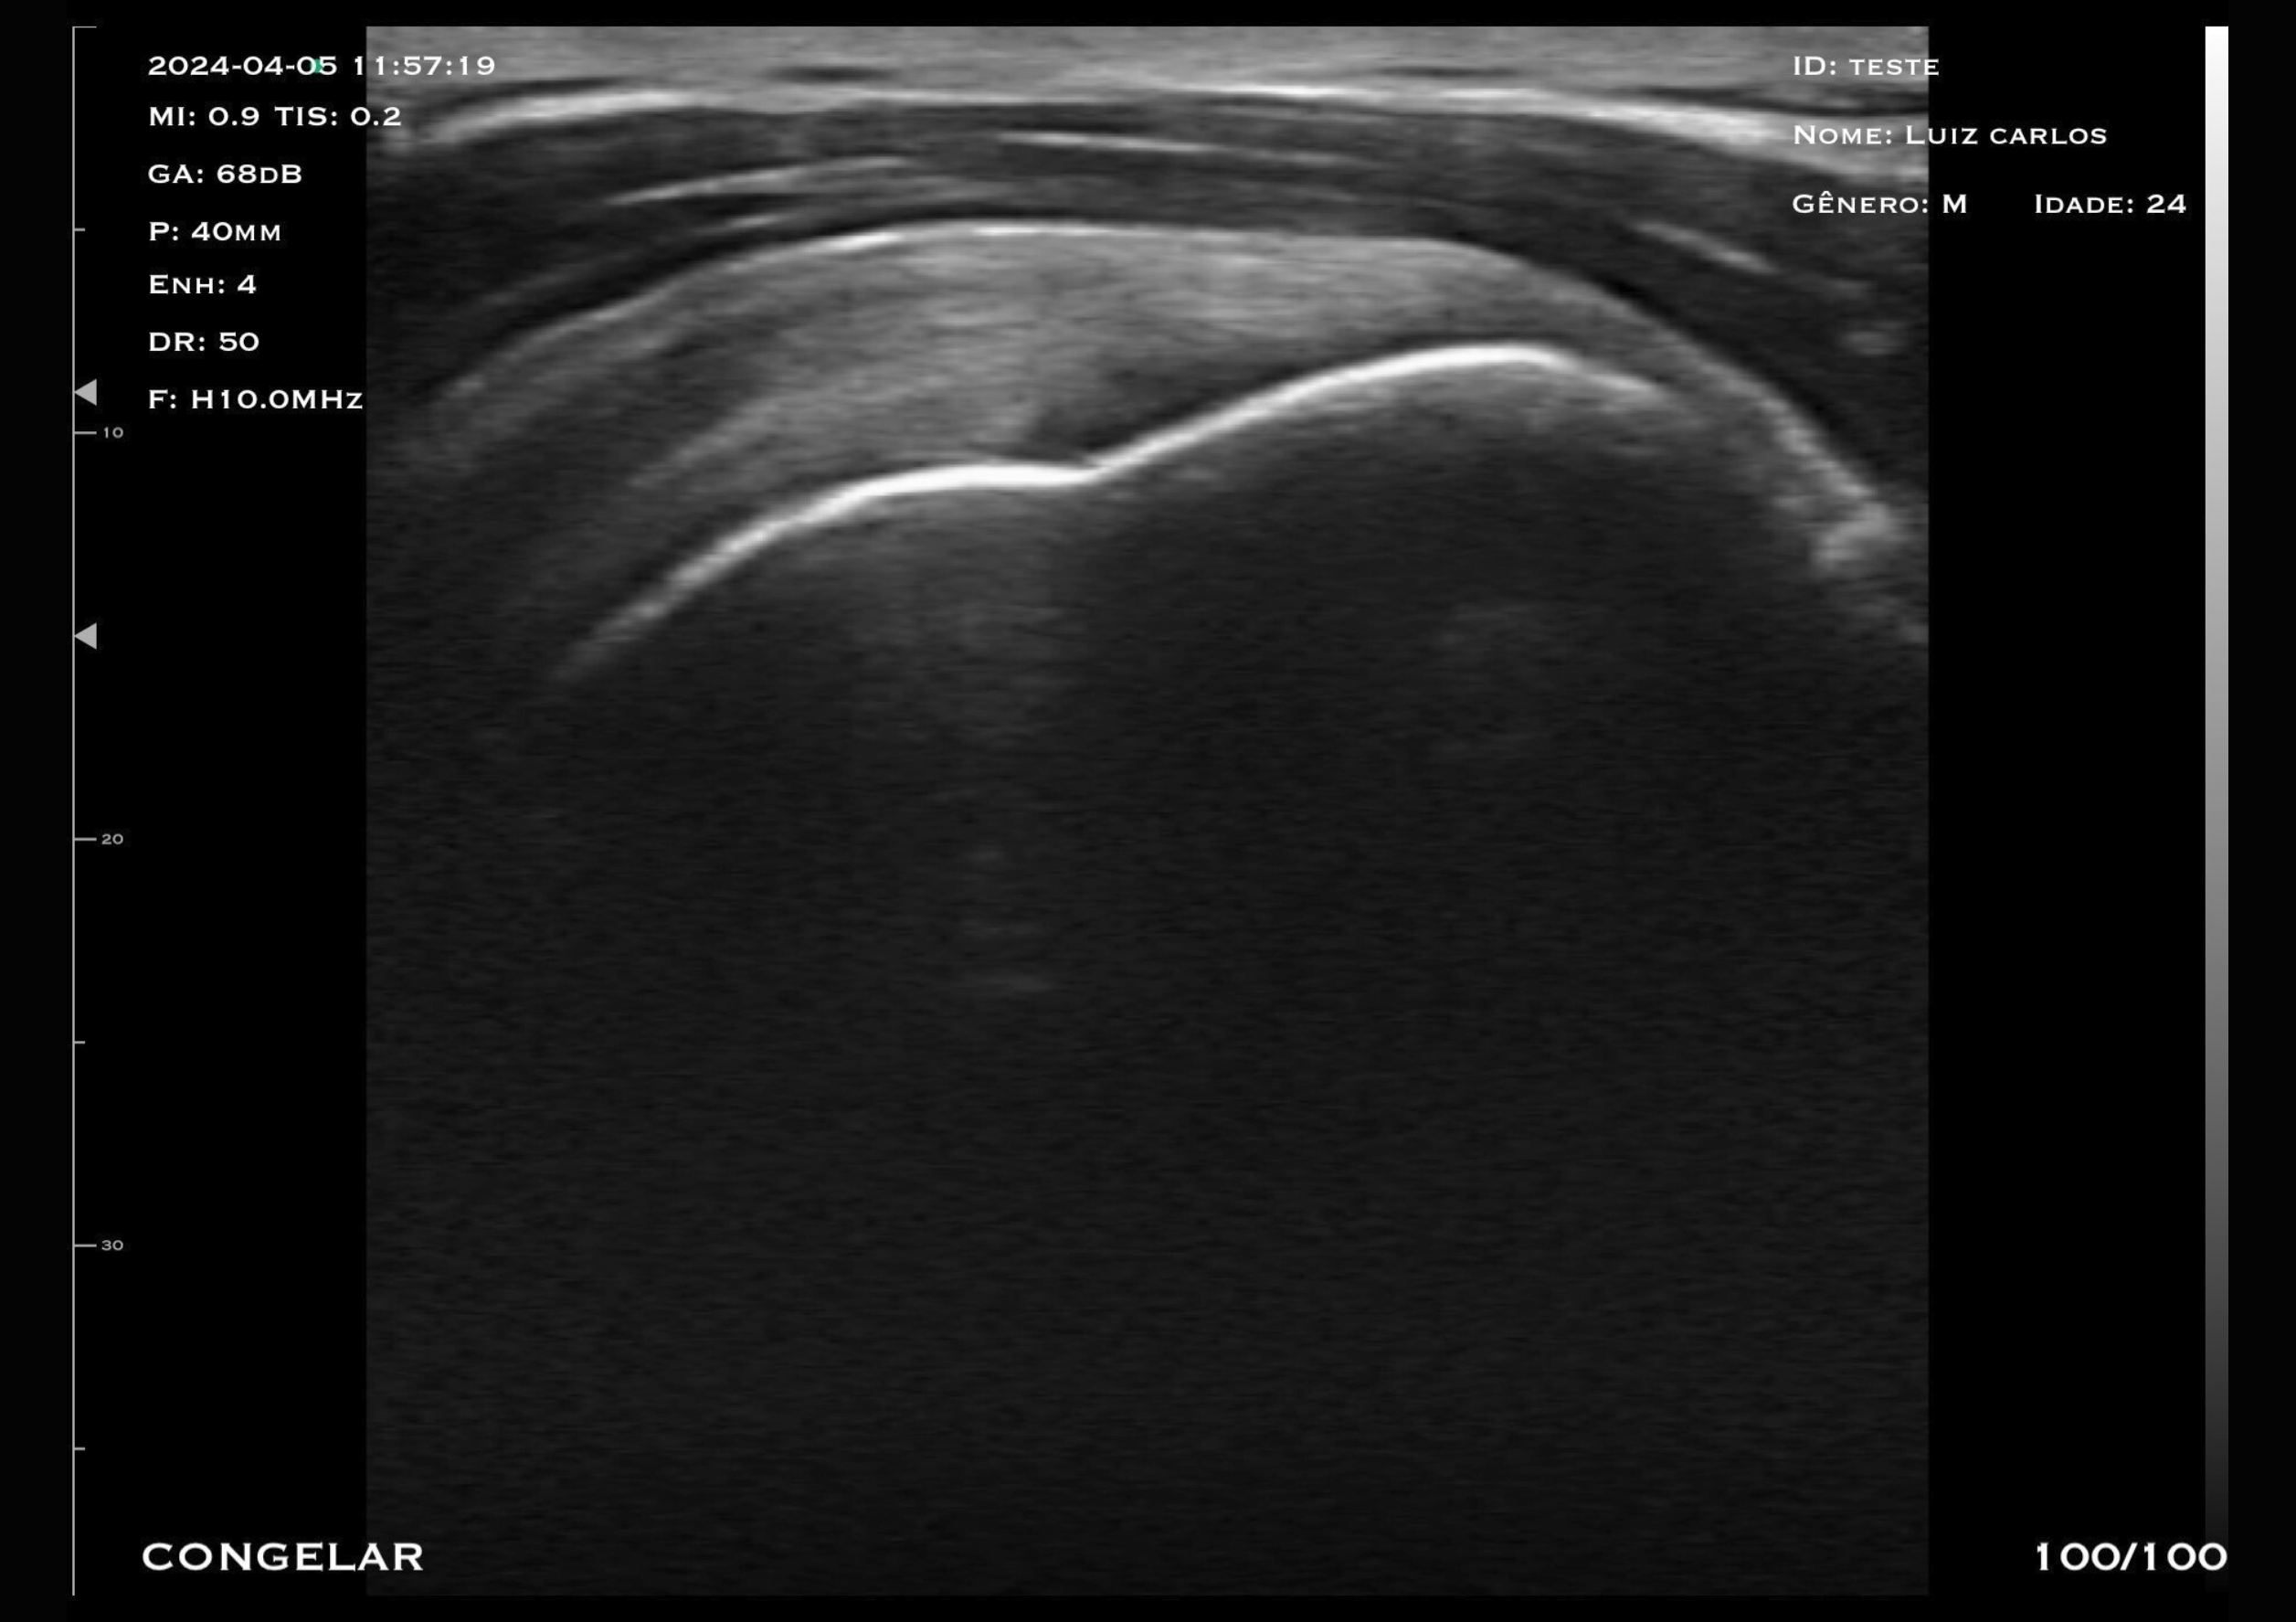

Com tecnologia linear e frequência de 7,5 a 10 MHz, o modelo M2HD é a escolha ideal para quem busca alta resolução em exames superficiais e intermediários, com foco em versatilidade e precisão.

O transdutor linear oferece imagens nítidas e detalhadas, permitindo a visualização precisa de estruturas como mama, tendões, músculos e articulações.

A frequência ajustável garante versatilidade para diferentes tipos de exames, desde avaliações mastológicas até procedimentos ortopédicos.